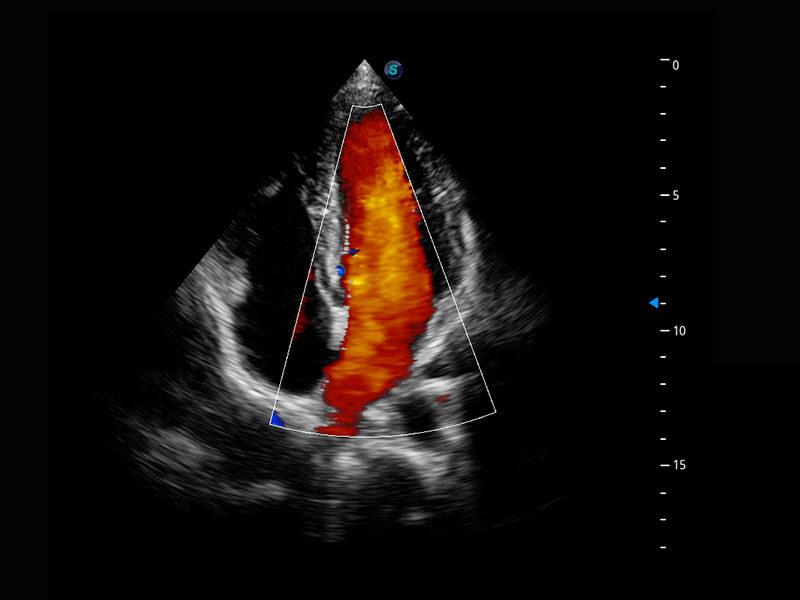

P60搭载一系列胎儿心脏成像技术,实现精细的胎儿心脏评估。

胎心容积成像